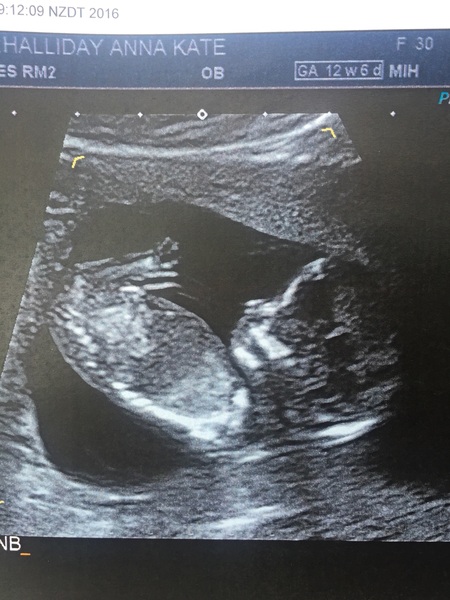

AnnaKateNZ · 25/09/2016 23:24

I had my twelve week scan this morning (NZ time). So amazing to see its wee heart beating and legs kicking around! They dated me 12w4d when I thought I was 12w6d. I don't know where they get the two days difference but there we go!

Great news AnnaKate Smile

I can never get tired of seeing scan pictures Smile

Neither, they are amazing aren't they Celen

Lovely clear scan AnnaKate

Lovely scan annakate.

Great scan anna!!

Morning ladies, Just catching up from the weekend. great to see another lovely scan anna